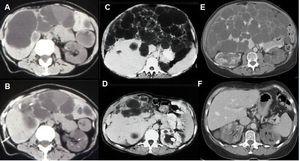

El carcinoma de células renales no es una causa frecuente de dolor en pacientes con PQRAD. La frecuencia no es superior a la de la población general, aunque puede presentarse a una edad más temprana, con frecuentes síntomas constitucionales y una proporción más elevada de tumores sarcomatoides, bilaterales, multicéntricos y metastásicos (figura 6). Frente a la presencia de una masa sólida en la ecografía o una masa con calcificaciones espiculadas en la TC o en la RM, y captación de contraste en la TC, se debe sospechar un carcinoma.

Figura 6. Tomografía computarizada de una paciente mujer de 62 años de edad.